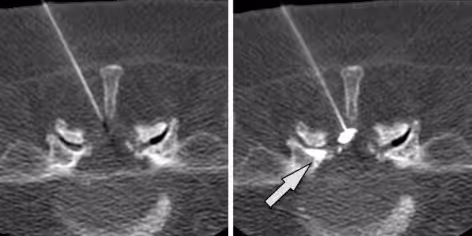

X-ray image showing the placement of a needle in the spine during a medical procedure.

Step 2: X-Ray Image Guidance

Medical image guidance (fluoroscopy/X-ray) is used to visualize the spine and guide the needle to the correct location near the facet joint.

CT scan of a spine shows a needle targeting a spinal area, with an arrow indicating the entry point.

Step 4: Needle Targets Facet Joint

The needle is advanced until it reaches the facet joint capsule. Contrast dye may be injected to confirm proper needle placement within the joint space.